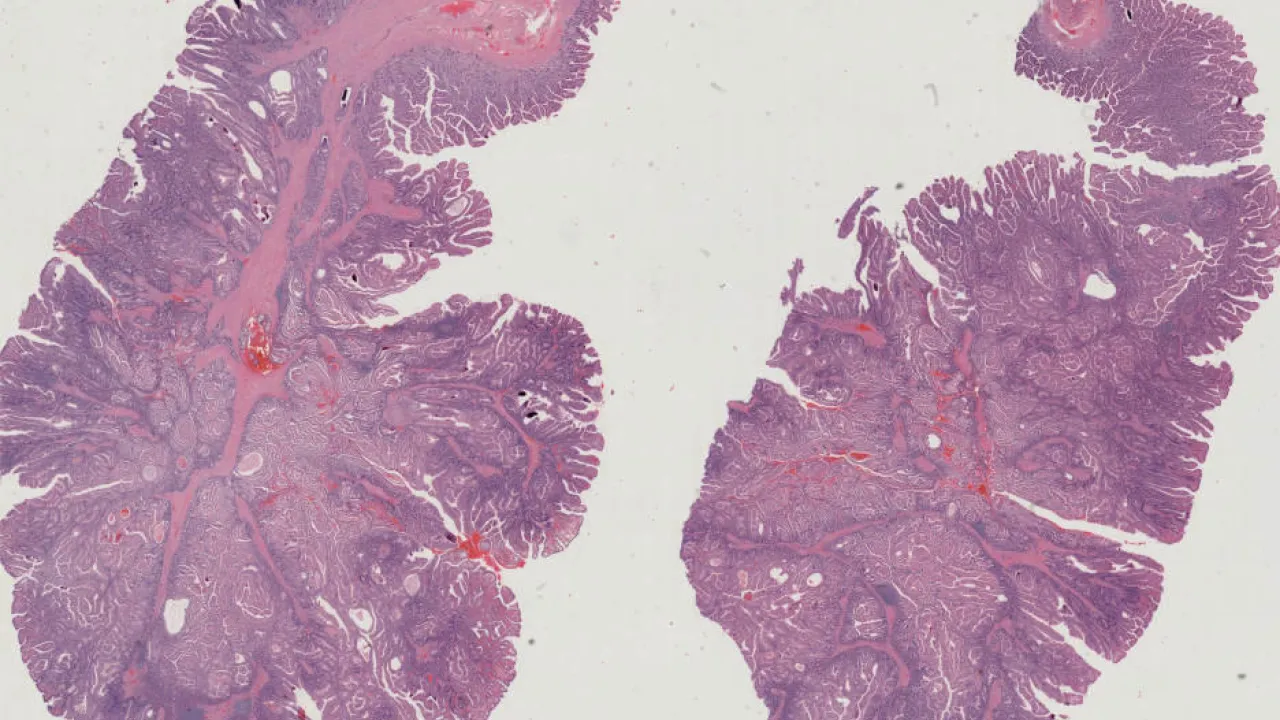

Small Intestine, Peutz-Jeghers polyp